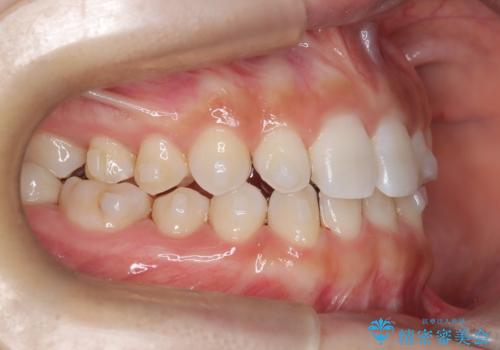

- 空隙歯列を主訴に来院された患者様です。

ばらけている空隙を一箇所に集めながら咬合や正中を改善して最後に補綴治療を行なっています。

右上の臼歯クロスバイトは骨格生のため、そのままにしています。